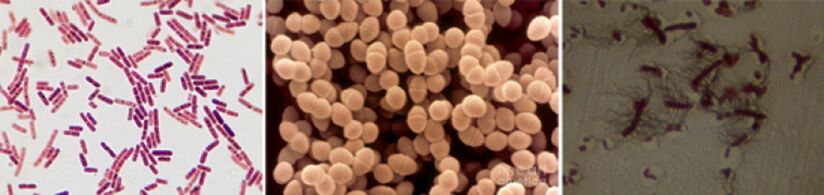

Unter den ursächlichen Wirkstoffen chronischer Prostatitis werden die folgenden Krankheitserreger gefunden:

- In 90% der Fälle zeigt die Krankheit solche gramnegativen Bakterien wie Escherichia coli (E. coli), Enterococcus faecalis (Fäkalerokokkus), etwas seltener - pseudomonas aeruginosa, klebsiella spp., Proteus spp., Prooteus spp. Pseudomonas aeruginosa, Enterobacter aerogenes und acinetobacter spp. Kamera -positive Bakterien von Enterosococci, Streptococci und Staphylococci sind selten.

- Die Rolle des Koagulasis-negativen Staphylokokken, der Harnstoff, Chlamydien, Trichomonia, Gardnerell, anaeroben Bakterien und Pilzen der Gattung Candida wurden nicht schließlich geklärt.